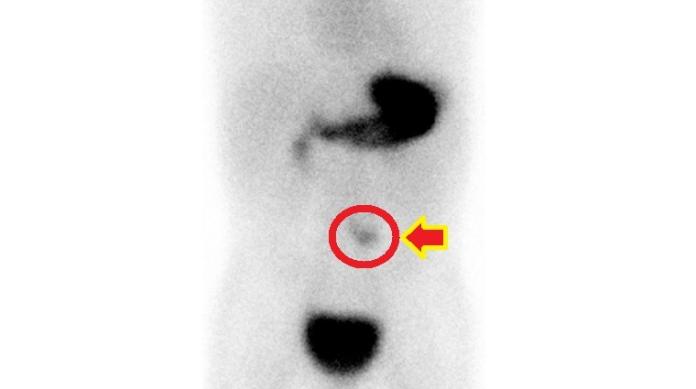

幼童持續血便且腹痛加劇,家長千萬別大意,因為這有可能是小腸先天性異常。5歲的楊小弟最近2天因反覆嘔吐與肚子痛被送到急診,醫師安排住院後開始解出磚紅色血便,而且皮膚與結膜變得蒼白。抽血檢查發現有貧血現象,經腹部電腦斷層與梅克爾核醫掃描檢查,診斷為梅克爾憩室。

梅克爾憩室診斷主要靠梅克爾核醫掃描檢查,顯示異位性胃黏膜組織,若出現臨床症狀,以手術切除為主要治療方式。梅克爾憩室或其併發症因早期症狀不典型,臨床上易與腸胃炎混淆。徐千婷醫師呼籲,若孩子出現大片血便,或嚴重腹痛等異狀,應盡早就醫檢查,及時治療。